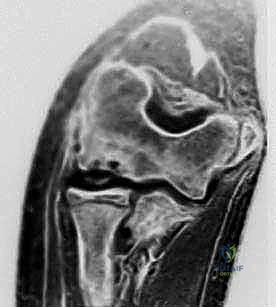

- التصوير بالرنين المغناطيسي (MRI): هو المعيار الذهبي لتقييم حالة الغضروف السطحي ومدى ثبات القطعة العظمية. يوفر الرنين المغناطيسي صوراً مفصلة للأنسجة الرخوة والوذمة العظمية (Bone edema).

- الأشعة المقطعية (CT Scan): قد تُطلب في الحالات المعقدة للتخطيط الجراحي الدقيق، حيث توفر خريطة ثلاثية الأبعاد لحجم وموقع الآفة العظمية.